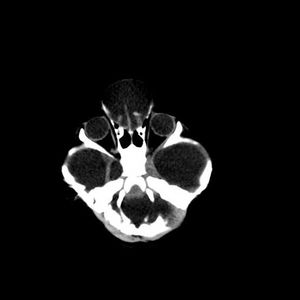

Clinical History: A 54-year-old man presented with upper lid swelling, conjunctival chemosis, and proptosis of the right eye.